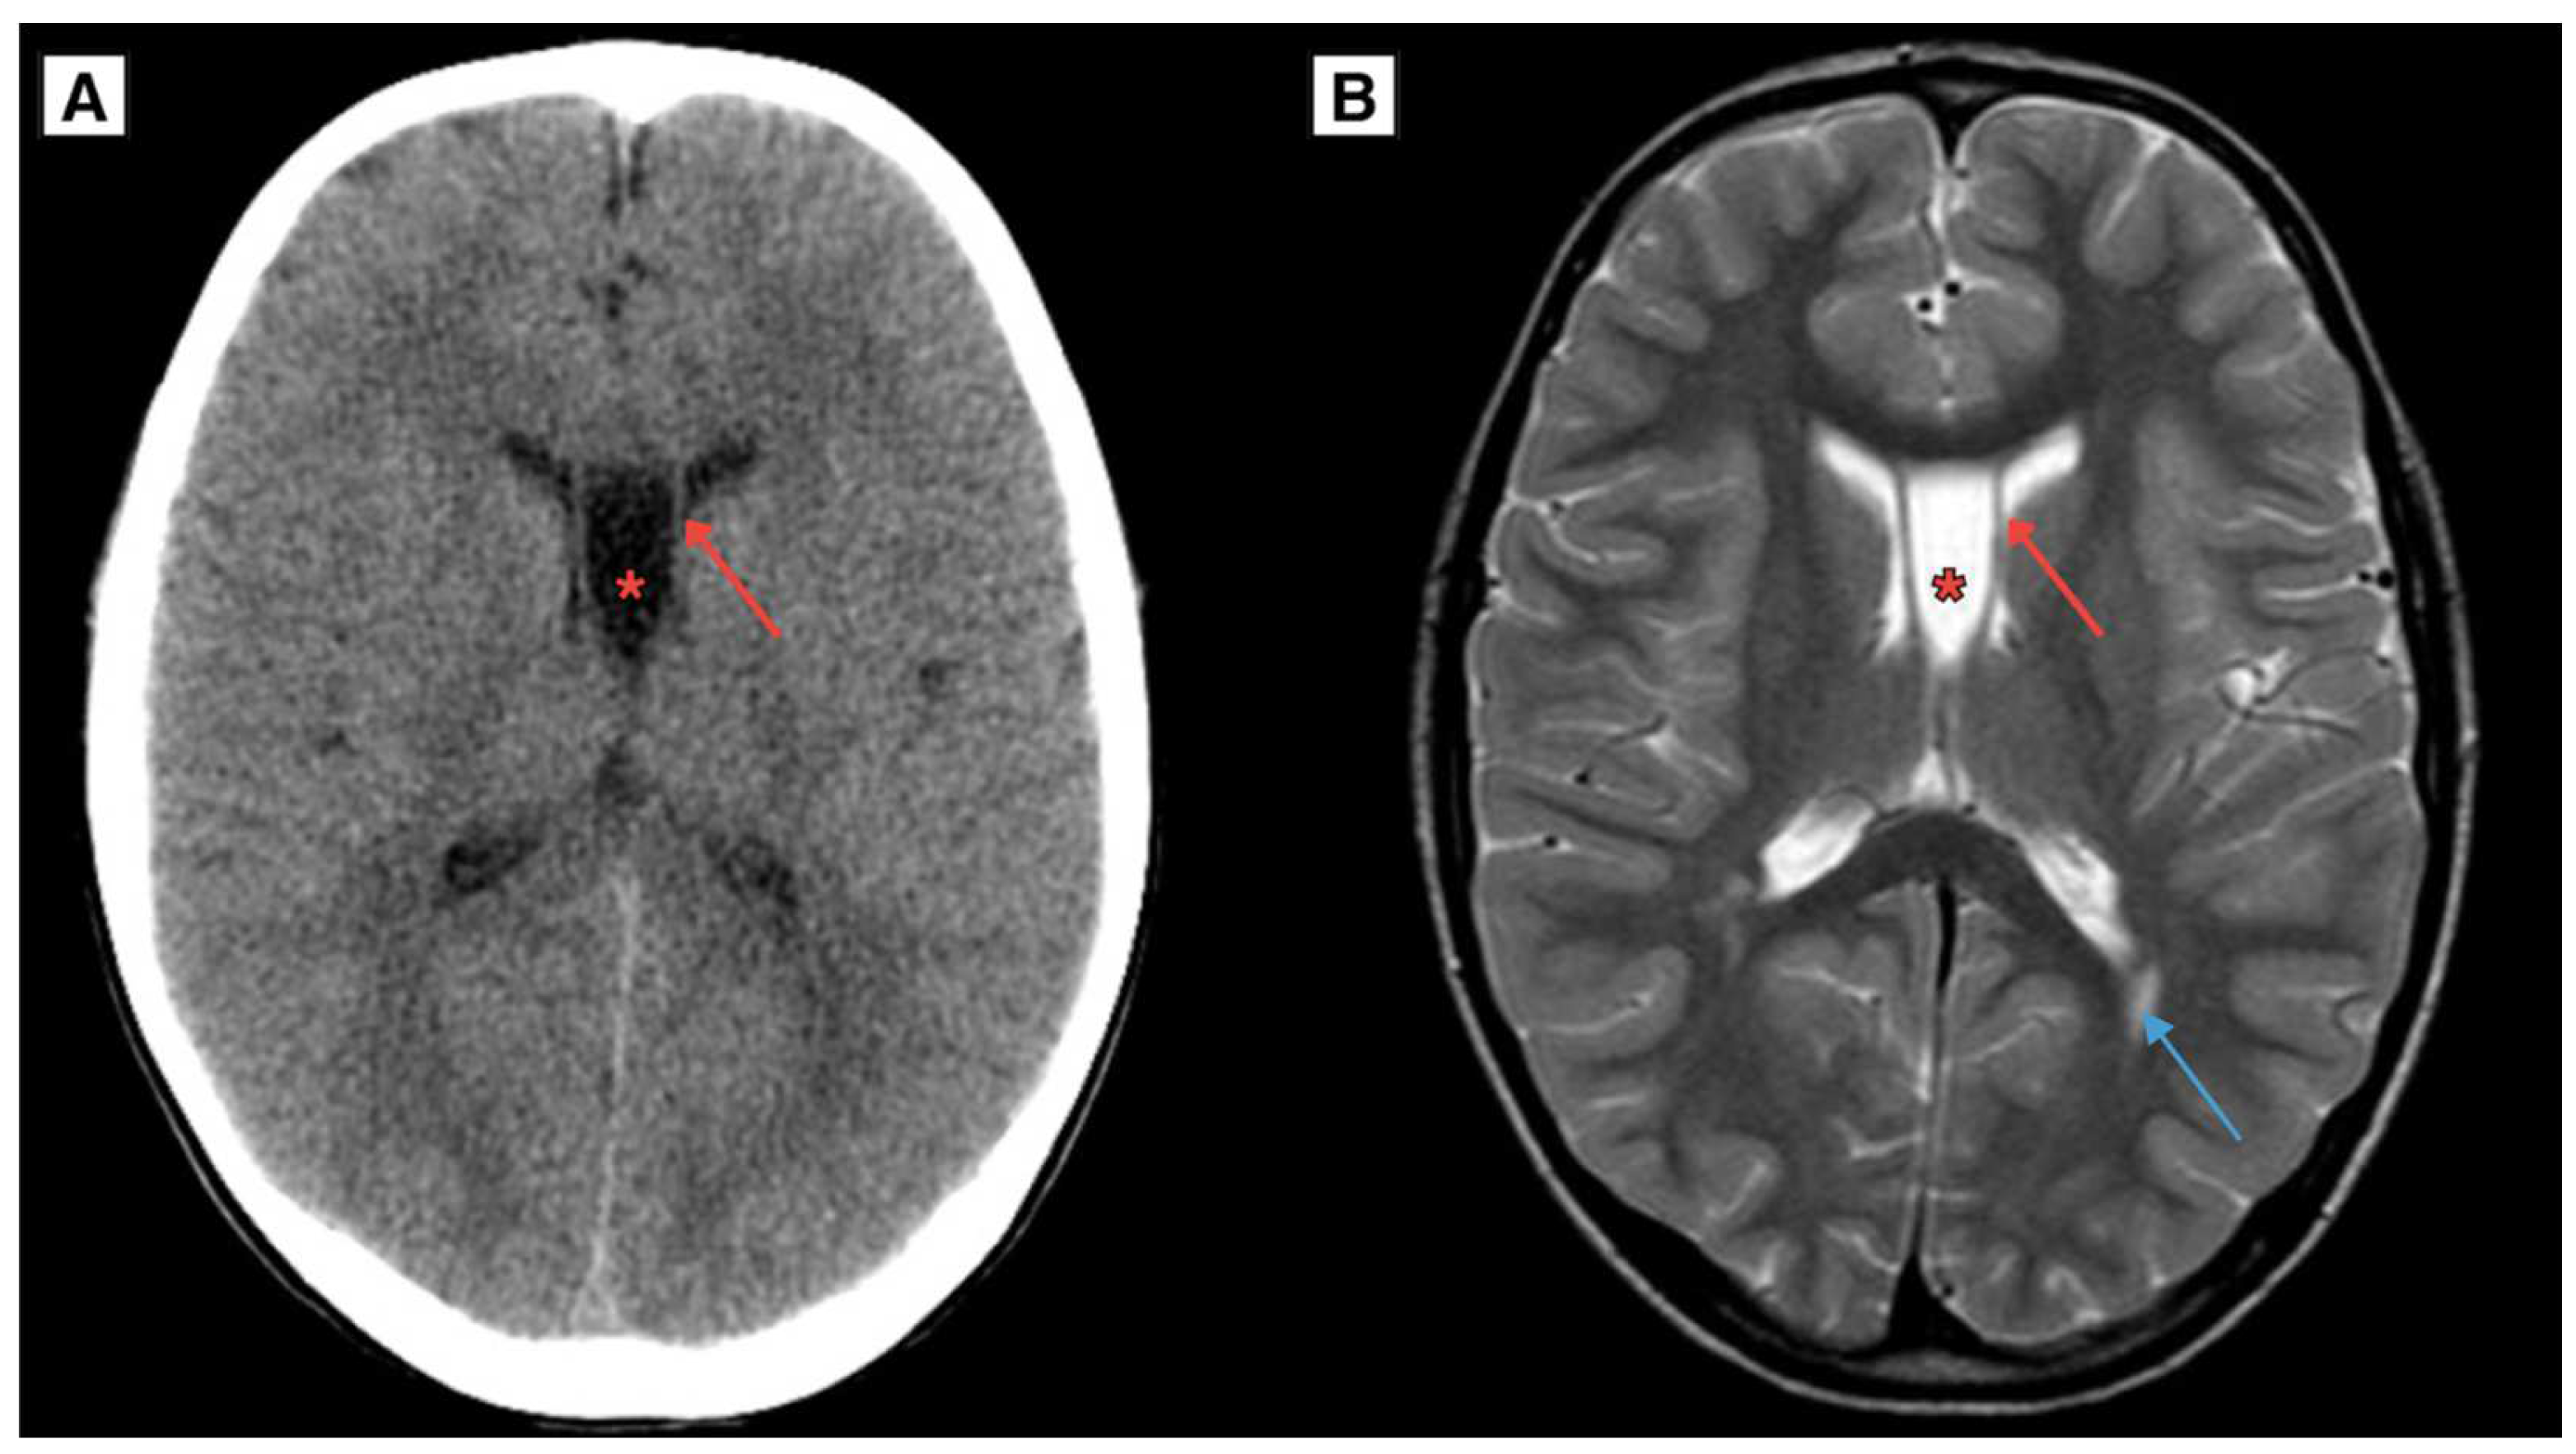

2.1. Retrospective imaging Review

2.2. A Novel Anatomical Pattern in CSP Cyst Imaging